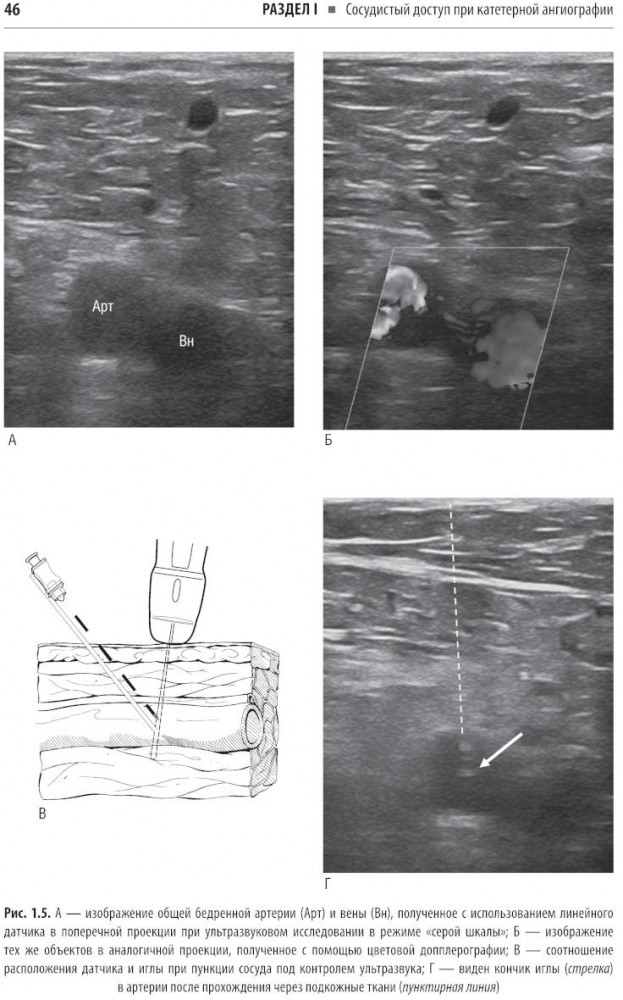

💳 Оплатить за товар можно при получении 🇰🇿 Есть бесплатная доставка по Казахстану 🎁 Копите бонусы с каждой покупки Справочник охватывает все ключевые аспекты, необходимые для успешной практики: показания, противопоказания, подготовку, технику выполнения, ведение пациентов после процедуры, а также профилактику и лечение возможных осложнений. В нем уделено особое внимание протоколам и оборудованию, что позволяет уверенно выполнять сложные манипуляции. Дана информация о сестринском деле, лекарственных препаратах и дозировках, что поможет обеспечить безопасность и комфорт пациентов. Простые линейные рисунки иллюстрируют анатомию и ход процедур, облегчая понимание сложных тем. Представлены сведения о катетерной ангиографии, трансартериальных и трансвенозных процедурах, а также о ведении пациентов во время процедуры. Издание предназначено рентгенохирургам, врачам любых хирургических специальностей, анестезиологам-реаниматологам, клиническим ординаторам и студентам медицинских вузов. Товар бережно упакован в пупырчатую плёнку и картонную коробку для защиты от механических повреждений. |